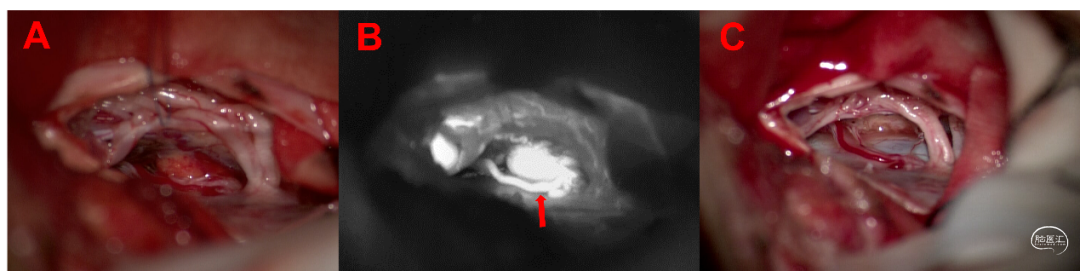

患者全麻满意后取俯卧位,消毒铺巾,导航定位,神经电生理监测,以C1-2为中心取约5cm直切口,切开皮肤,剥离双侧椎旁肌肉,暴露C1-2棘突及椎板,磨钻磨除C1后弓及C2左侧椎板上缘,椎板咬钳咬除黄韧带,扩大骨窗,完成椎管减压,剪开硬脊膜悬吊,松解蛛网膜,沿左侧探向脊髓腹侧,于左前方见血管性结节,上下相邻血管扩张明显,提示血供丰富,质软,形态不规则,约1cm×1cm×1cm大小,基底嵌入髓内,外生型生长偏向左侧,考虑为血管母细胞瘤。行术中荧光造影可见肿瘤上方有脊髓腹侧发出的血管进入肿瘤,依据造影结果先电凝阻断供血血管,悉心保护周围正常脊髓,沿病灶与脊髓界面从软膜下分离边界后,全切肿瘤。术区严密止血,松解粘连神经根。神经电生理监测提示双下肢MEP可及,与术前对照相仿。取6-0 proline镜下严密硬脊膜,硬膜外止血后逐层缝合肌肉及皮肤,手术结束,术中出血约20ml。